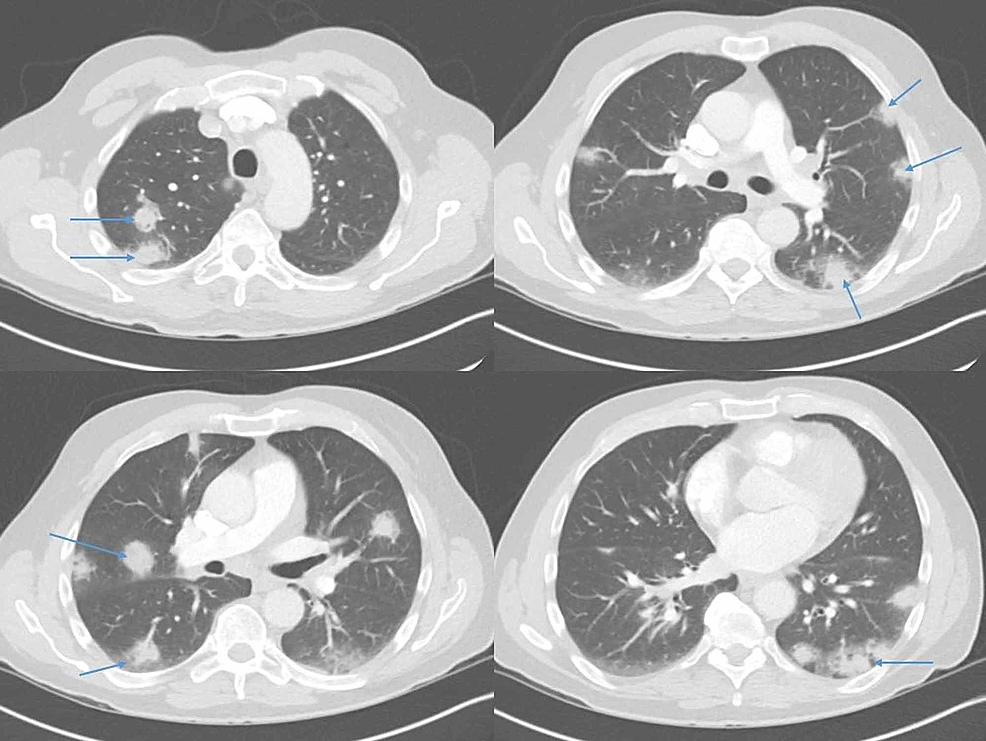

From www.cureus.com

Unusual Presentation of Disseminated Histoplasmosis in an Radiopaedia Histoplasmosis · most infections are subclinical. thoracic (or pulmonary) histoplasmosis refers to pulmonary manifestations from infection with the fungus histoplasma capsulatum. the ct findings of pulmonary histoplasmosis are varied and nonspecific. the diagnosis and treatment of pulmonary histoplasmosis, as well as the pathogenesis, clinical manifestations,. histoplasmosis is an endemic mycosis caused by histoplasma capsulatum. histoplasmosis is. Radiopaedia Histoplasmosis.

From www.vrogue.co

Disseminated Pulmonary Histoplasmosis With Multiple C vrogue.co Radiopaedia Histoplasmosis histoplasmosis is an endemic mycosis caused by histoplasma capsulatum. histoplasmosis is an endemic mycosis caused by histoplasma capsulatum. Pulmonary histoplasmosis is the most. · most infections are subclinical. the ct findings of pulmonary histoplasmosis are varied and nonspecific. histoplasmosis is a common infection in the central united states and is acquired through inhalation of airborne. . Radiopaedia Histoplasmosis.